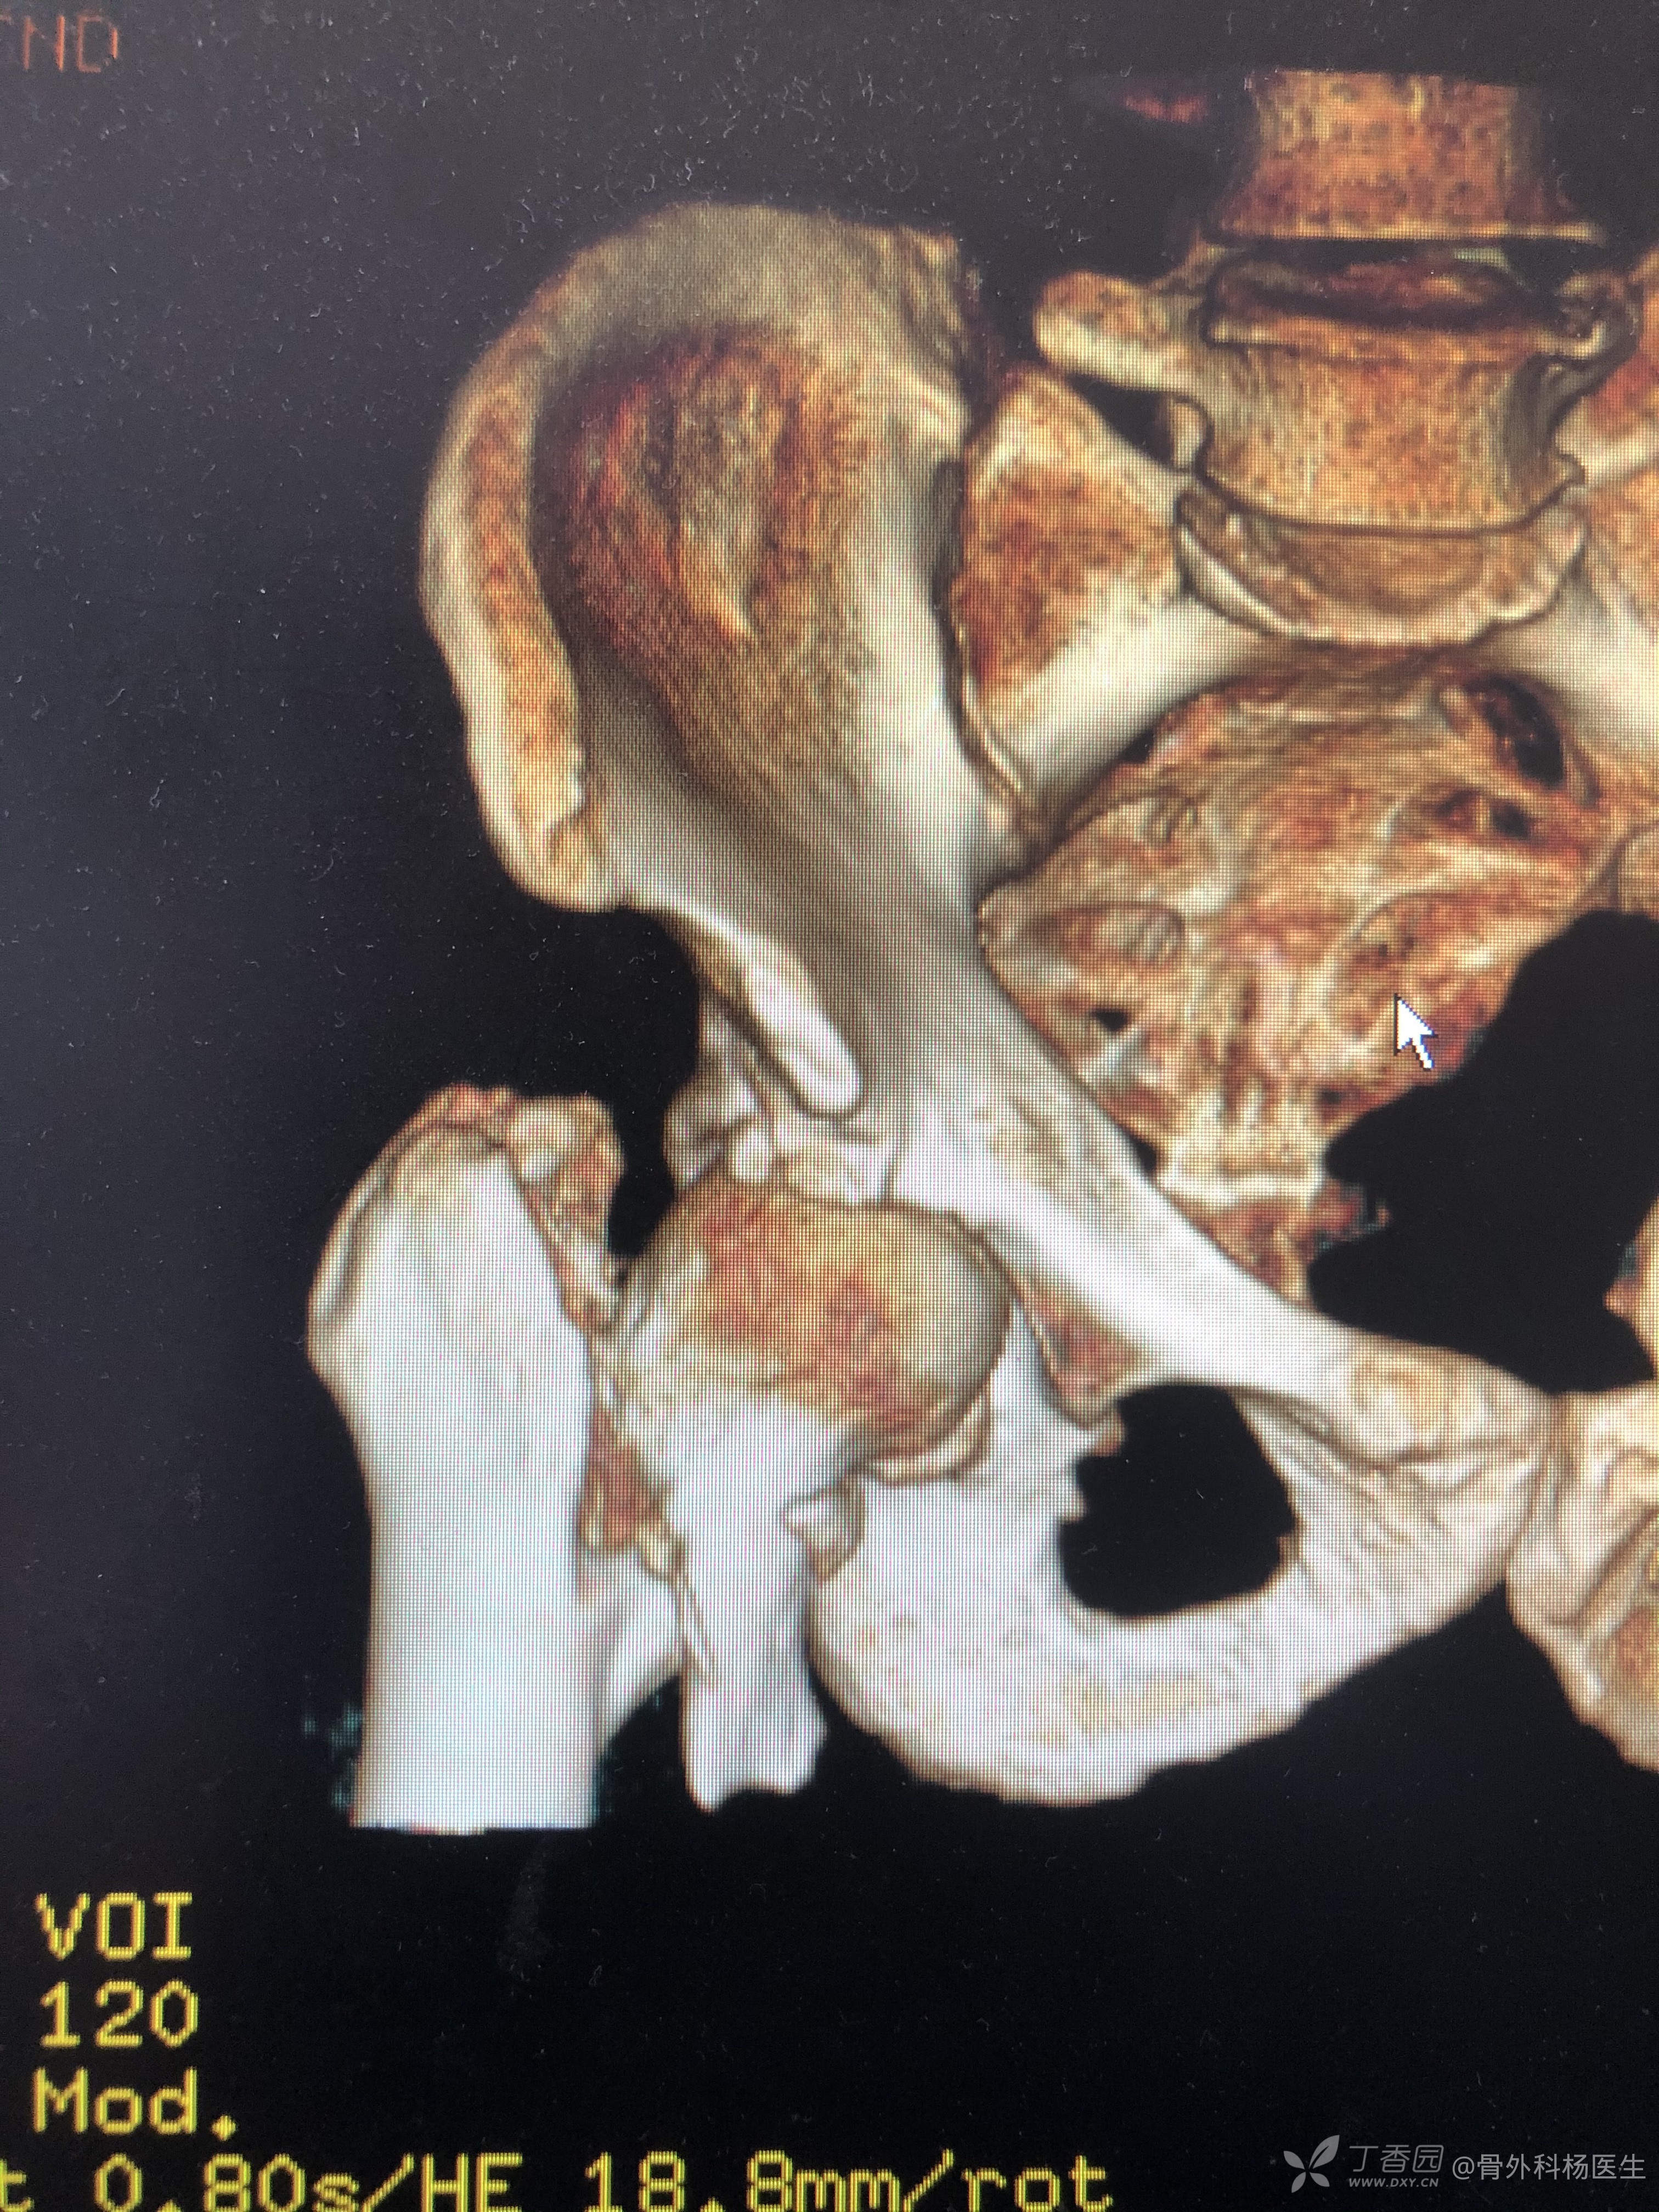

A1.3 骨折线经过小转子下方,如下图:

多见于年轻且骨质较好的患者。

因为髂腰肌的作用,很难牵引床复位,一般需要切开复位。

上牵引床,果然近折端向后侧移位,越加大牵引,移位约厉害。